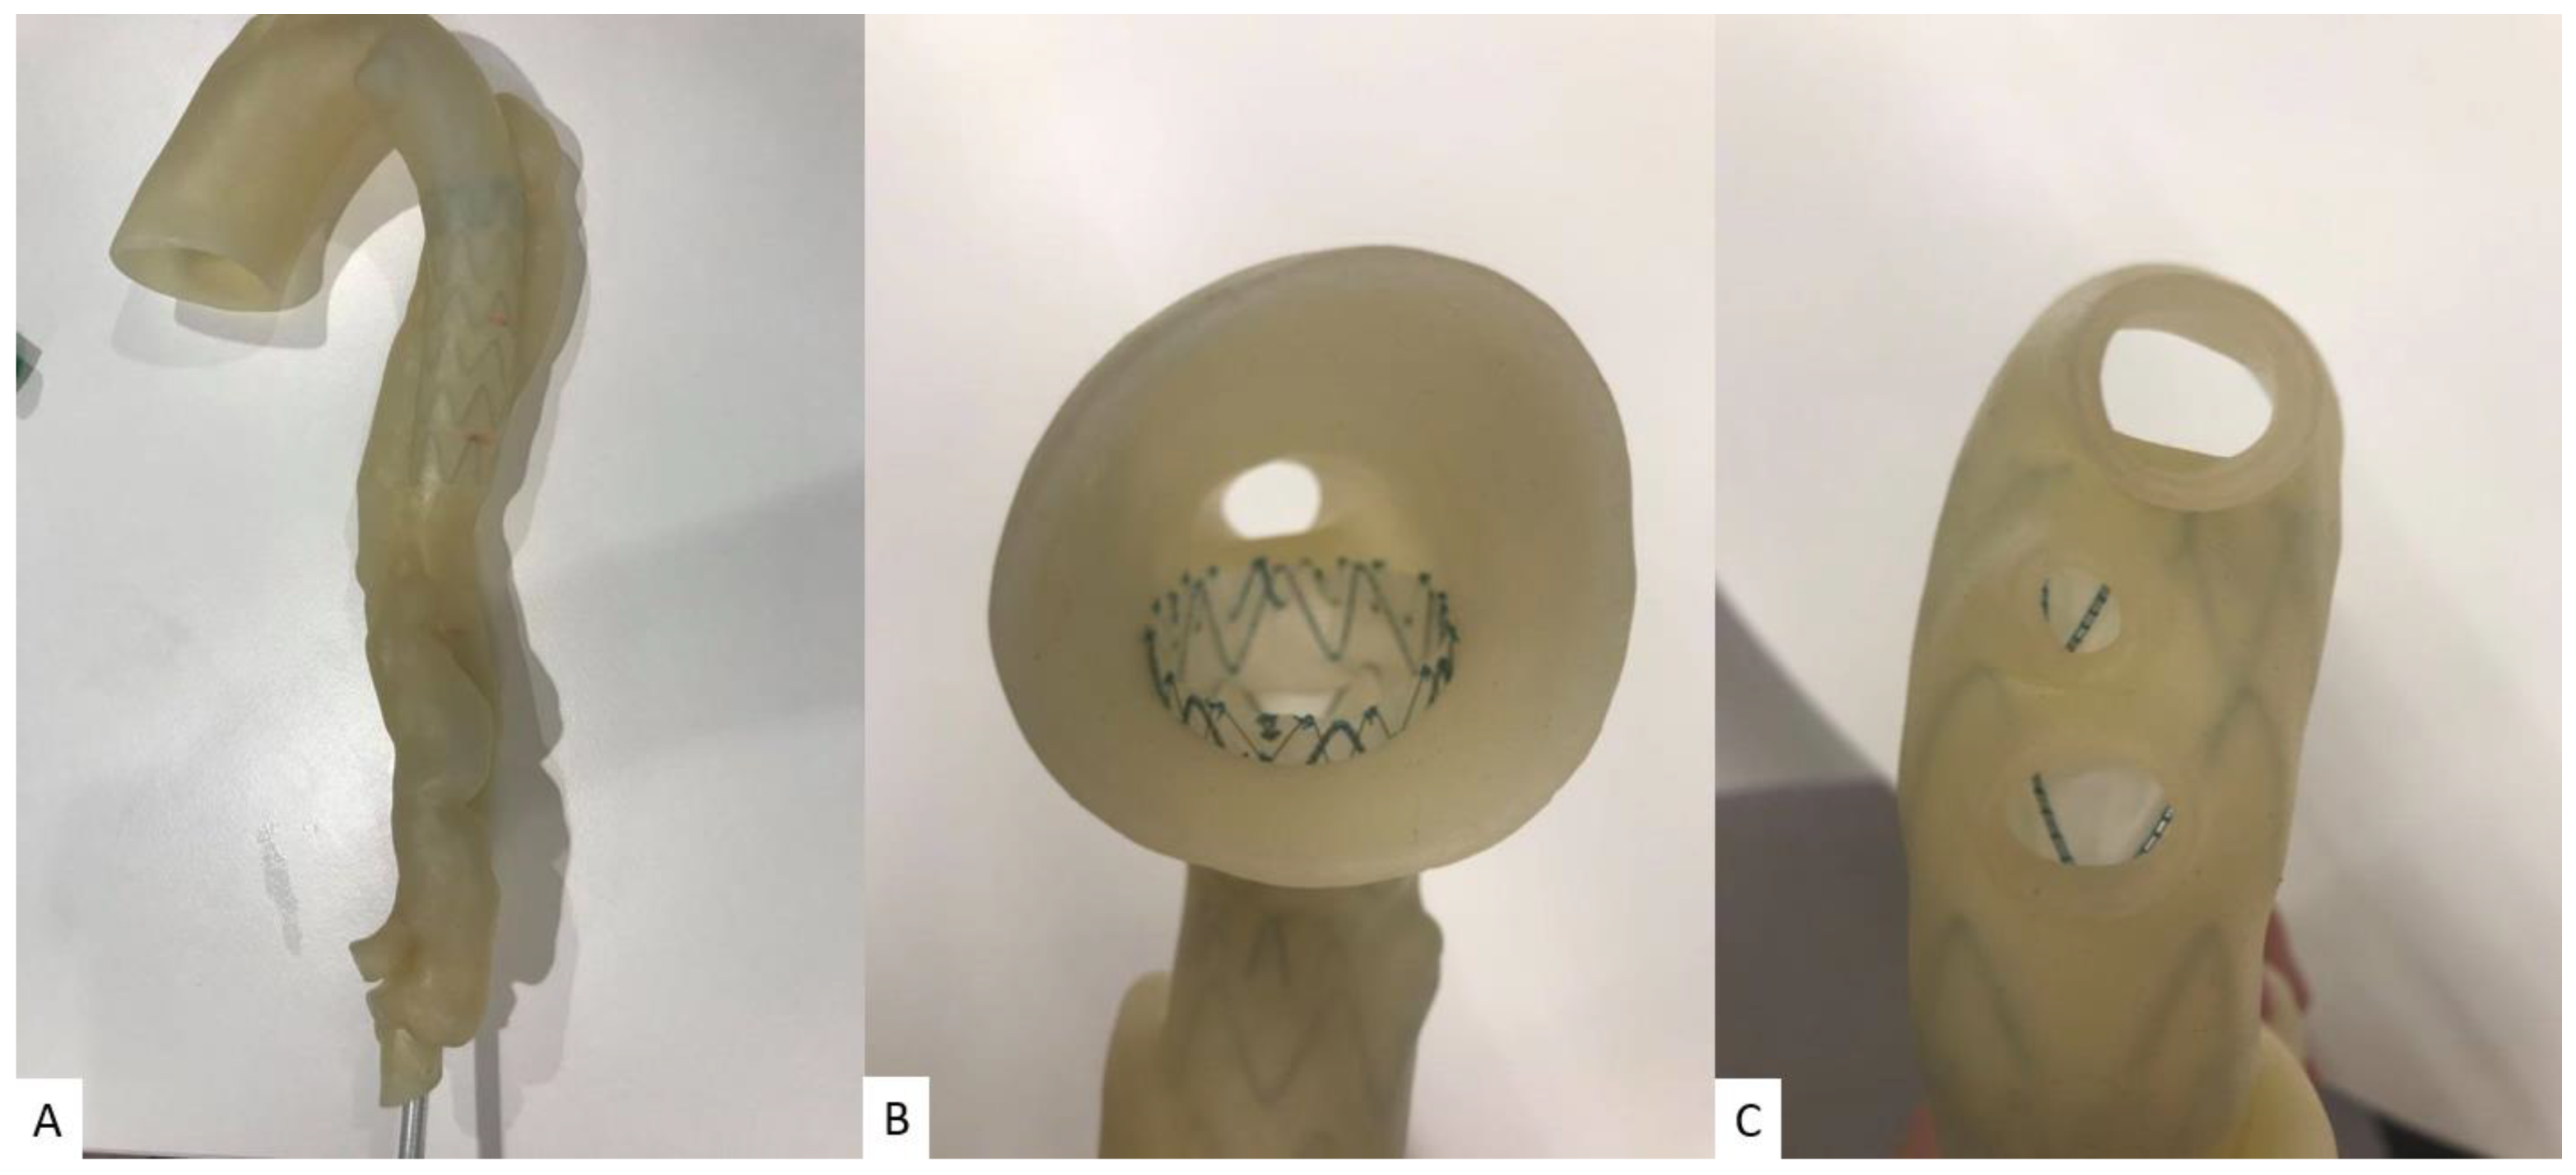

5.1. 3D-Printed Breast Cancer Model

- Sindi, R.; Wong, Y.H.; Yeong, C.H.; Sun, Z. Development of patient-specific 3D-printed breast phantom using silicone and peanut oils for magnetic resonance imaging. Quant. Imaging Med. Surg. 2020, 10, 1237–1248. [Google Scholar] [CrossRef]

- Sindi, R.; Wong, Y.H.; Yeong, C.H.; Sun, Z. Quantitative measurement of breast density using personalized 3D-printed breast model for magnetic resonance imaging. Diagnostics 2020, 10, 793. [Google Scholar] [CrossRef]

- He, Y.; Liu, Y.; Dyer, B.A.; Boone, J.M.; Liu, S.; Chen, T.; Zheng, F.; Zhu, Y.; Sun, Y.; Rong, Y.; et al. 3D printed breast phantom for multi-purpose and multi-modality imaging. Quant. Imaging Med. Surg. 2019, 9, 63–74. [Google Scholar] [CrossRef]

| Breast | 1 | MRI | Breast cancer model for breast MRI protocols | Printer: Breast skin shell was printed using Raise3D N2 Plus; Fibroglandular tissues were printed using Anycubic Photon S Materials: Breast skin shell was printed PLA; Fibroglandular tissues were printed using Magma H LINE Photopolymer Resin Cost: USD 30 for breast skin shell and USD 25 for fibroglandular tissues | Breast skin shell was printed at a resolution of 12.5 μm for the x and y-axis planes; 10 μm for z-axis plane Fibroglandular tissues were printed at a resolution of 47 μm for the x, y and z-axis planes Time: ~40 h for breast skin shell and 50 h for fibroglandular tissues |